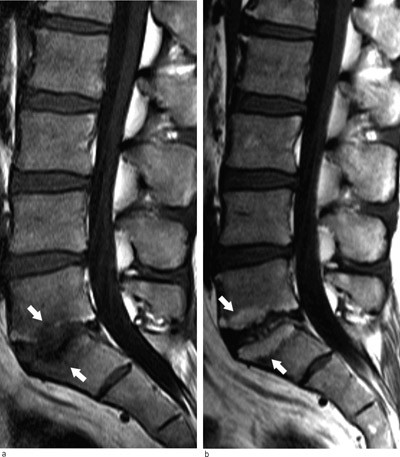

Inn mot degenerative mellomvirvelskiver kan man på MR se signalforandringer i dekkplatene og i beinmargen i tilstøtende virvelcorpora. Dette kalles Modic-forandringer og er vanligst i nivåene L4/L5 og L5/S1 (21). Det er to hovedtyper av disse beinmargsforandringene. Type 1 har lavt signal på T1-vektede bilder og høyt signal på T2-vektede som uttrykk for en inflammatorisk reaksjon med beinmargsødem. Type 2 har høyt T1-signal og høyt T2-signal som tegn på fettomdanning av den røde beinmargen.

I en systematisk litteraturoversikt var median prevalens av Modic-forandringer 43 % hos pasienter med smerter lavt i ryggen og/eller isjias, men bare 6 % i normalpopulasjonen (22). En dansk populasjonsstudie av 40-åringer viste at det var sammenheng mellom Modic-forandringer og forekomst av uspesifikke smerter lavt i ryggen (15). Slike beinmargsforandringer er ikke stabile. Over tid kan type 1 overgå til type 2, men de kan også forsvinne av seg selv (23) (fig 4). Den kliniske betydningen av Modic-forandringer er fortsatt usikker. Eventuelle terapeutiske konsekvenser undersøkes i pågående studier.